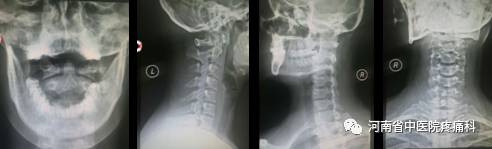

【辅助检查】血常规:(-)。颈椎四位片示:颈椎生理曲度轻度反弓,棘突偏歪,骨质增生。

【专科检查】颈椎生理曲度变浅,颈2-7椎旁两侧、双侧肩胛骨内上角压痛明显,局部肌肉质硬,棘突偏歪;颈椎功能活动度:前屈(15°)、后伸(10°)、左侧屈(20°)、右侧屈(20°),左旋(25°),右旋(25°),椎间孔挤压试验阴性,臂丛牵拉试验阴性,霍夫曼征阴性,双上肢肌力正常,运动感觉尚可,余未见明显异常。发作时VAS评分8分。